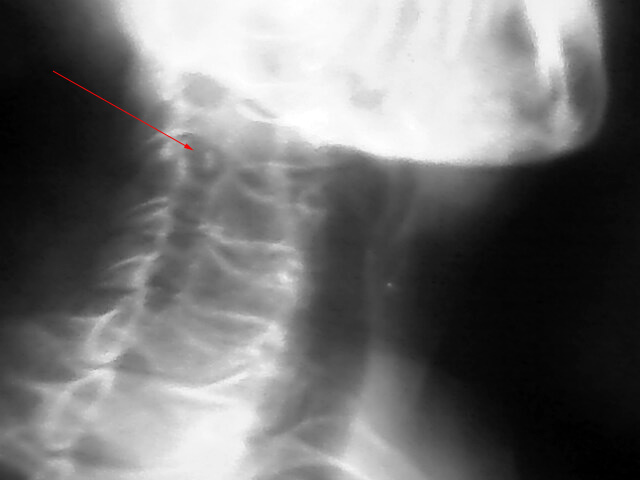

以下是引用拾荒者在2009-8-26 20:37:00的发言:[br]箭头所指为椎后韧带钙化或游离髓核钙化可能。

以下是引用jiangguowu在2009-8-26 21:28:00的发言:[br]加照对侧斜位,没有的话考虑软组织钙化或体外异物,如有则考虑椎后韧带钙化或游离髓核钙化